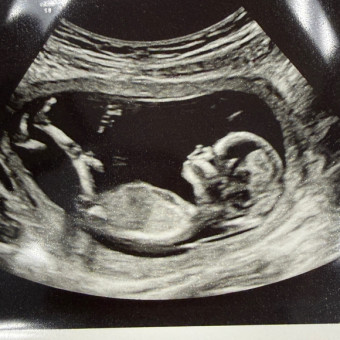

Our little bundle is on the way! We’ve got love covered, but could use a little help with the gear, the diapers, and maybe a nap or two. 💖